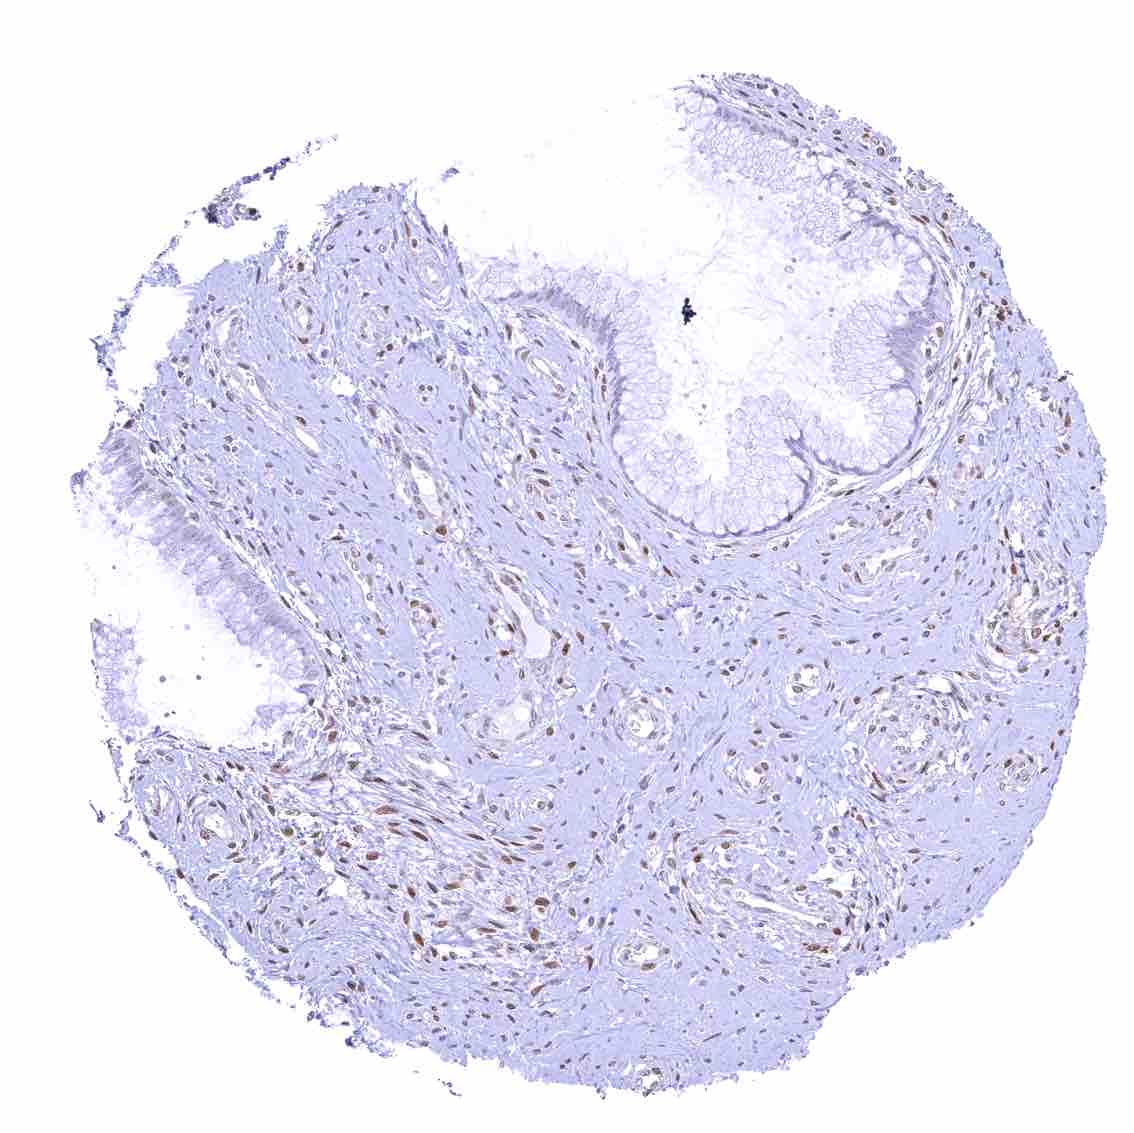

Uterus, ectocervix – Nuclear staining of squamous epithelial cells predominates in the more mature cell layers (top 50_ of the epidermis).